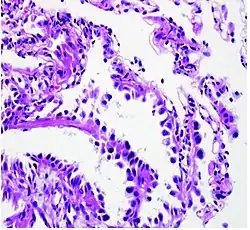

Histopathology

If possible, a biopsy of any suspected lung tumor is performed to make a microscopic evaluation of the cells involved and is ultimately required to confirm diagnosis.[7] Biopsy should be attempted in distant lesions first to establish a histologic diagnosis and to simultaneously confirm metastatic staging. The biopsy material is also used to analyze whether the tumor express any specific mutations suitable for targeted therapy (e.g. EGFR mutation or ALK mutation). Biopsy can be accomplished via bronchoscopy, transthoracic needle biopsy, and video-assisted thorascopic surgery (VATS).[4]

While sputum cytology has been shown to have limited utility, thoracentesis, or aspiration of pleural fluid with an ultrasound-guided needle, should be performed when pleural effusion is present. When malignant cells are identified in the pleural aspirate of patients highly suspect for lung cancer, a definitive diagnosis and staging (stage IV adenocarcinoma of the lung) is established.[4]

Adenocarcinoma of the lung tends to stain mucin positive as it is derived from the mucus-producing glands of the lungs. Similar to other adenocarcinoma, if this tumor is well differentiated (low grade) it will resemble the normal glandular structure. Poorly differentiated adenocarcinoma will not resemble the normal glands (high grade) and will be detected by seeing that they stain positive for mucin (which the glands produce). Adenocarcinoma can also be distinguished by staining for TTF-1, a cell marker for adenocarcinoma.[29]

As discussed previously, the category of adenocarcinoma includes are range of subtypes, and any one tumor tends to be heterogeneous in composition. Several major subtypes are currently recognized by the World Health Organization (WHO)[1] and the International Association for the Study of Lung Cancer (IASLC) / American Thoracic Society (ATS) / European Respiratory Society (ERS):[30][31][32] lepidic predominant adenocarcinoma, acinar predominant adenocarcinoma, papillary predominant adenocarcinoma, micropapillary predominant adenocarcinoma, solid predominant adenocarcinoma, and solid predominant with mucin production. In as many as 80% of these tumors, components of more than one subtype will be recognized. Surgically resected tumors should be classified by comprehensive histological subtyping, describing patterns of involvement in increments of 5%. The predominant histologic subtype is then used to classify the tumor overall.[2] The predominant subtype is prognostic for survival after complete resection.[33]

To reveal the adenocarcinomatous lineage of the solid variant, demonstration of intracellular mucin production may be performed. Foci of squamous metaplasia and dysplasia may be present in the epithelium proximal to adenocarcinomas, but these are not the precursor lesions for this tumor. Rather, the precursor of peripheral adenocarcinomas has been termed atypical adenomatous hyperplasia (AAH).[10] Microscopically, AAH is a well-demarcated focus of epithelial proliferation, containing cuboidal to low-columnar cells resembling club cells or type II pneumocytes.[10] These demonstrate various degrees of cytologic atypia, including hyperchromasia, pleomorphism, prominent nucleoli.[10] However, the atypia is not to the extent as seen in frank adenocarcinomas.[10] Lesions of AAH are monoclonal, and they share many of the molecular aberrations (like KRAS mutations) that are associated with adenocarcinomas.[10]